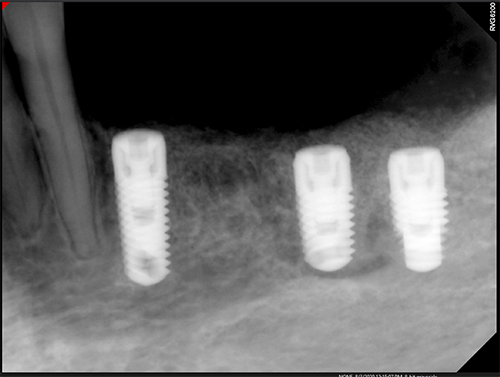

Ridge Split Mandibular Left and Right with Implants